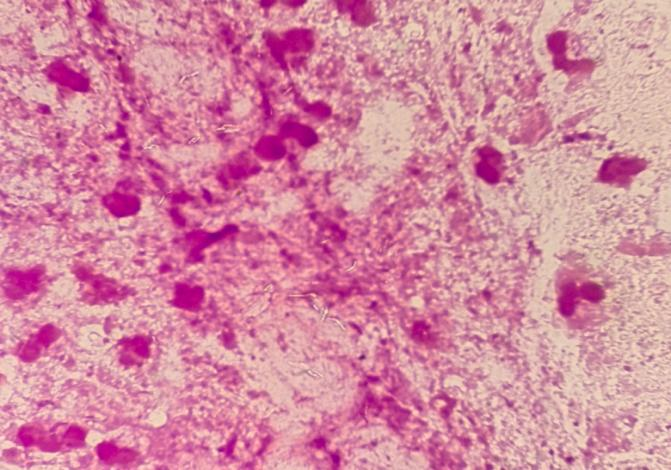

案例一:患者,男性,56岁,出现肺部感染症状,诊断为重症肺炎,送检痰培养,经48小时培养为上呼吸道正常菌群生长。但涂片经革兰染色镜下观察可见大量白细胞,且白细胞内外均可见未着色杆状菌,俗称“鬼影”,怀疑分枝杆菌感染,重新制片进行抗酸染色,结果镜下可见大量抗酸杆菌。立即与临床沟通,建议进行结核及利福平耐药基因检测,两小时即出结果,明确病原菌为结核分枝杆菌,未检测到利福平耐药基因,至此通过一张简单快速的涂片染色即为临床诊疗提供了非常有价值的病原学信息。

案例二:患者,女性,38岁,出现阴道感染症状,分泌物呈黄脓色,临床送检淋球菌培养。在培养标本的涂片中发现大量革兰阴性小杆菌,白细胞内外均可见,随即加种血平皿及巧克力平皿,经72小时培养,淋病奈瑟菌培养未见生长,可见大量的阴道加德纳菌生长,成功帮助临床诊断为阴道加德纳菌引起的阴道炎。